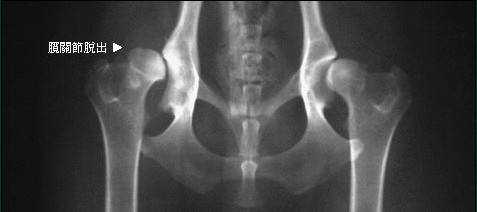

诊断犬髋关节形成不良需要直接的触诊和X光检查,早期诊断治疗有助于减轻疼痛,适当的用药并控制体重,可以有效控制病情。

1、髋关节发育不全是犬最常见的髋关节疾病之一,常见于大型的犬只,通常两侧的关节都会受到影响。